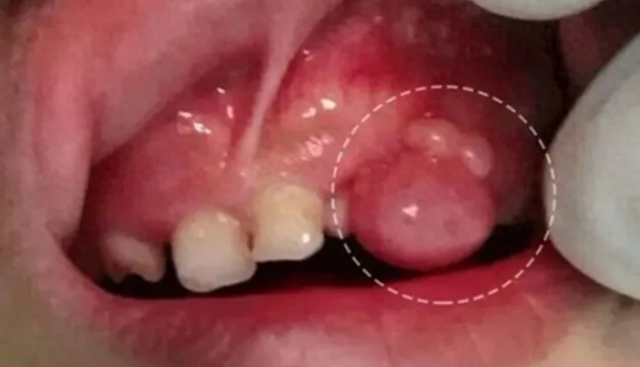

小朋友上牙龈长出了个肉包包有图慎入有懂的帮忙看下

牙龈长个包包是怎么回事呢?去医院看了,医生说是上火!真的只是上火吗?